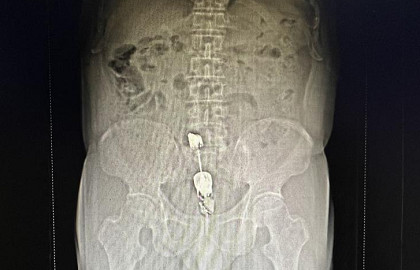

【黄播 科普】15cm的棒状物体塞入肛门,老汉腹坠胀难忍,黄播 成功施救

今年的9月9日是世界急救日。红十字会与红新月会国际联合会将每年9月的第二个周六定为“世界急救日”,这个纪念日旨在呼吁世界各国重视普及急救知识,让更多人掌握急救技能,在事发现场挽救生命和降低伤害程度。